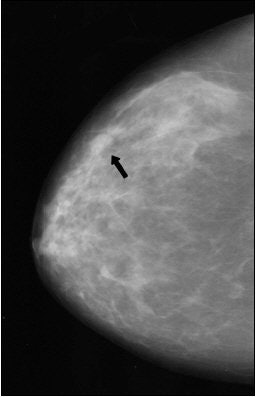

| Same patient. A digital magnification of the image above. Cancers in both left and right breasts were marked by CAD system. Butler SA, Gabbay RJ, Kass DA, Siedler DE, O'Shaughnessy KF, Castellino RA, "Computer-Aided Detection in Diagnostic Mammography: Detection of Clinically Unsuspected Cancers," (AJR 2004; 183: 1511-1515). |

In the end, the CAD system marked 87% of the biopsy-proven secondary cancers. More specifically, it caught 88% of the masses and 85% of the microcalcification clusters. The average number of false per four-view mammogram was 2.7, higher than the 2.0 reported for previous studies that tested CAD in a screening setting, the authors wrote. This is most likely explained by the fact that most known cancers are more complex, and under greater scrutiny by the CAD system, they wrote.